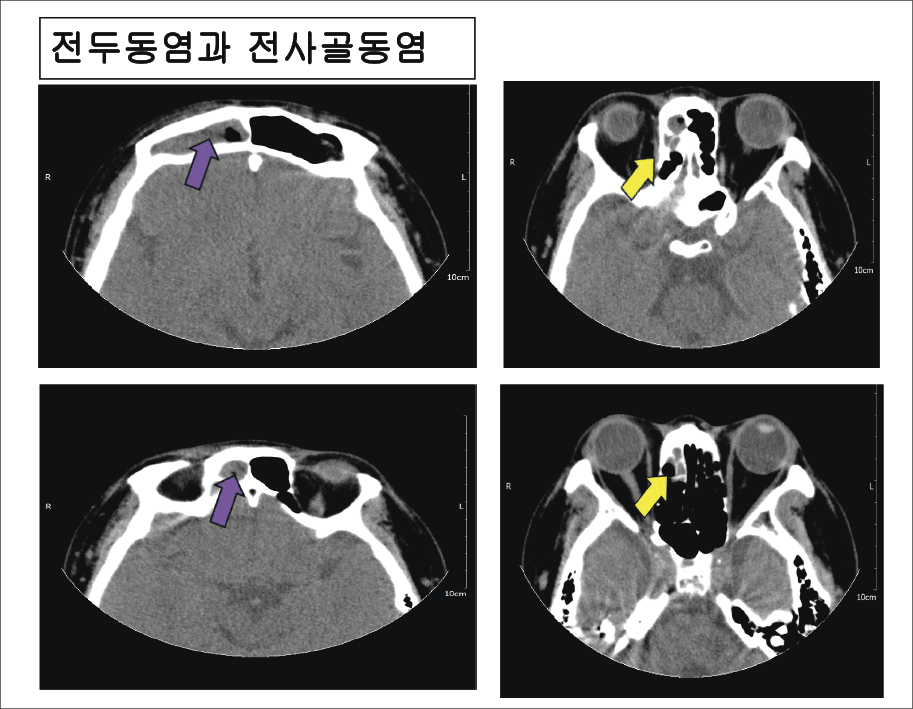

종합해 보니 전두동염을 의심할 수 있었고, 확인을 위해 CT 촬영을 진행했다.

CT 결과로는 우측 전사골동과 우측 전두동으로 저음영 소견이 보였다. 부비동염은 비염 같은 상기도 감염으로 시작하는 경우가 많아 대부분 상악동염을 동반하는데, 이 환자는 상악동은 깨끗하고 우측 전사골동과 전두동만 침범된 이유는 7월부터 시작한 수영과 직장에서의 에어컨 위치인 것으로 생각됐다.